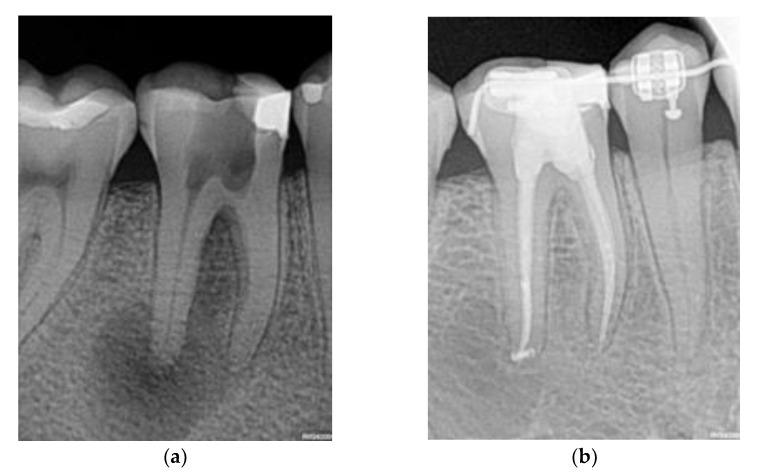

Although the association between risk factors and non-surgical root canal treatment (NSRCT) failure has been extensively studied, methods to predict the outcomes of NSRCT are in an early stage, and dentists currently make the treatment prognosis based mainly on their clinical experience. Since this involves different sources of error, we investigated the use of machine learning (ML) models as a second opinion to support the clinical decision on whether to perform NSRCT. We undertook a retrospective study of 119 confirmed and not previously treated Apical Periodontitis cases that received the same treatment by the same specialist. For each patient, we recorded the variables from a newly proposed data collection template and defined a binary outcome: Success if the lesion clears and failure otherwise. We conducted tests for detecting the association between the variables and the outcome and selected a set of variables as the initial inputs into four ML algorithms: Logistic Regression (LR), Random Forest (RF), Naive-Bayes (NB), and K Nearest Neighbors (KNN). According to our results, RF and KNN significantly improve (-values < 0.05) the sensitivity and accuracy of the dentist's treatment prognosis. Taking our results as a proof of concept, we conclude that future randomized clinical trials are worth designing to test the clinical utility of ML models as a second opinion for NSRCT prognosis.

尽管风险因素与非手术根管治疗(NSRCT)失败之间的关联已得到广泛研究,但预测NSRCT结果的方法尚处于早期阶段,目前牙医主要根据临床经验做出治疗预后判断。由于这涉及不同的误差来源,我们研究了使用机器学习(ML)模型作为第二种意见,以支持关于是否进行NSRCT的临床决策。我们对119例确诊且此前未接受过治疗的根尖周炎病例进行了回顾性研究,这些病例由同一位专家进行相同的治疗。对于每位患者,我们从新提出的数据收集模板中记录变量,并定义了一个二元结果:如果病变清除则为成功,否则为失败。我们进行了检测变量与结果之间关联的测试,并选择了一组变量作为四种ML算法的初始输入:逻辑回归(LR)、随机森林(RF)、朴素贝叶斯(NB)和K近邻(KNN)。根据我们的结果,RF和KNN显著提高(p值<0.05)了牙医治疗预后的敏感性和准确性。以我们的结果作为概念验证,我们得出结论,未来值得设计随机临床试验来测试ML模型作为NSRCT预后第二种意见的临床效用。